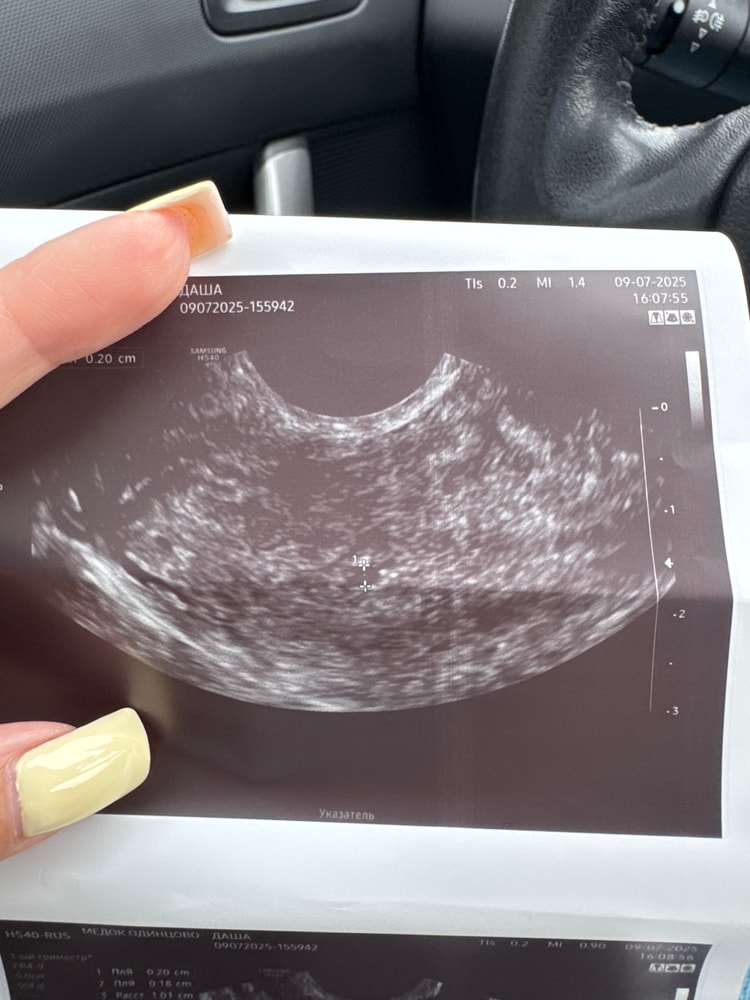

Это не пя, что за врач 😂

Это совсем не похоже на плодное яйцо.

Раздвоение Птичности, сказали что похоже очень ,и желтое тело у меня и хороший эндометрий

Елизавета, сказали либо пя либо скопление жидскости